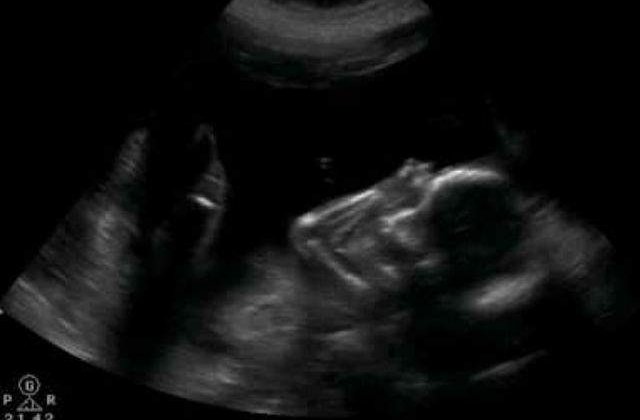

Fenomenul, extrem de rar, consta in faptul ca fatul creste si apoi moare in afara uterului. Din cauza ca nu poate fi eliminat fara ajutor din exterior, pentru a se proteja, organismul femeii a acoperit treptat fatul mort cu mai multe straturi de calciu, transformandu-l intr-un „bebelus de piatra”, explica medicii.

Femeia spune ca a ramas insarcinata acum mai bine de 40 de ani si pentru ca a avut dureri in timpul sarcinii a cerut ajutorul unui vraci. Dupa ce si-a administrat remediul primit, femeia a observat ca „burta nu i-a mai crescut si ca bebelusul nu a mai miscat” si a crezut ca a fost avortat, povesteste ginecologul care a consultat-o recent pe octogenara, scrie usatoday.com.